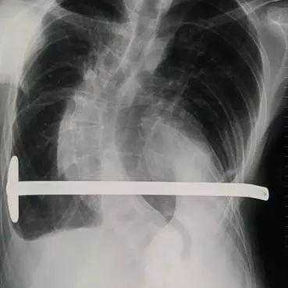

​First, the adhesions were thoroughly released, and a portion of the protruding ribs and costal cartilage at the top of the protrusion was cut off. By lifting and pressing down, the chest wall was adjusted to its normal height. Second, three MatrixRIBs was used to replace the removed rib sections, and their curvature was carefully adjusted to closely resemble the normal curvature of the chest wall, thereby completing the reconstruction of the thoracic cage. Third, a bar was placed and flipped within the chest wall to elevate the most depressed part of the central chest wall. Lastly, two bars were placed on and secured to the bone surface of the lower half of the chest wall. The surgery achieved a satisfactory result, eliminating the deformities and restoring the chest wall to its normal shape.